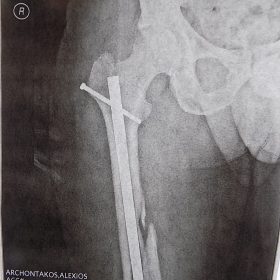

Τα κατάγματα της Διάφυσης των οστών της κνήμης και του Μηριαίου οστού στη σύγχρονη ΟΡΘΡΟΠΑΙΔΙΚΗ αντιμετωπίζονται με ΕΝΔΟΜΥΕΛΙΚΗ ΗΛΩΣΗ.

Δύο τομές 3 εκατοστών και 1 εκατοστού αντιστοίχως για την εισαγωγή και το κλείδωμα του ήλου μέσα στο οστό. Η μέθοδος είναι κλειστή,σχεδόν αναίμακτη,διάρκειας 60 λεπτών,με τη βοήθεια C-ARM (τηλεόρασης).